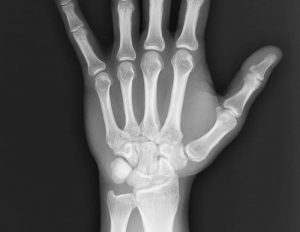

Перелом кисти руки диагностируется более чем в 30% случаях обращения к травматологу с нарушением целостности костей. В любой травматичной ситуации человек старается защититься, выставив ладони перед собой, что объясняет высокую распространенность травмы. Тяжелое повреждение кисти проявляется яркой симптоматикой, которая схожа с сильным ушибом. Несмотря на характерные клинические проявления, для уточнения диагноза применяется рентгенографическое исследование.

Первоначально определение вида травмы основано на внешних проявлениях. Травматолог осматривает поврежденный участок, выслушивает жалобы пострадавшего, уточняет время и подробности травмы. Учитывая то, что по общим признакам перелом кисти руки во многом схож с вывихом и сильным ушибом, проводится аппаратное исследование с помощью рентгеновского снимка.

При этом для большей информативности рентгенография назначается в двух проекциях. В некоторых случаях из-за сильного отека признаки перелома не визуализируются. Тогда диагностика откладывается на 8-10 дней, а на время ожидания рука обездвиживается при помощи жесткой повязки из гипса или полимерных бинтов.

Если при повторной рентгенографии перелом подтверждается, травматолог определяет метод дальнейшего лечения с учетом характера травмы, возраста и здоровья пациента.